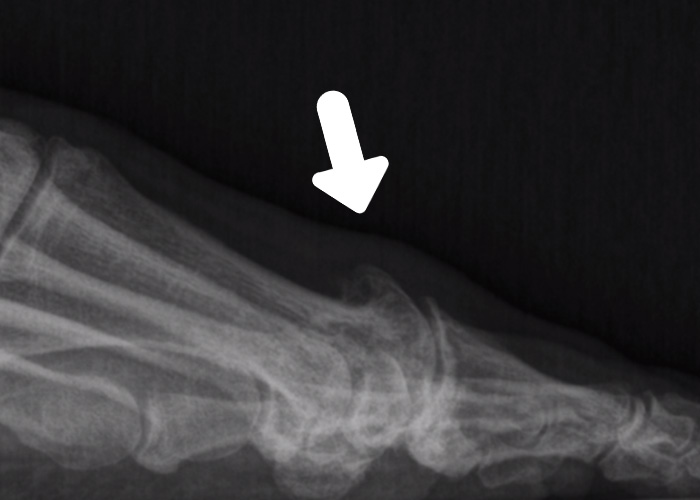

Antes y después

Te mostramos algunos ejemplos de antes y después de resolución de hallux rigidus con cirugía mínimamente invasiva del pie.